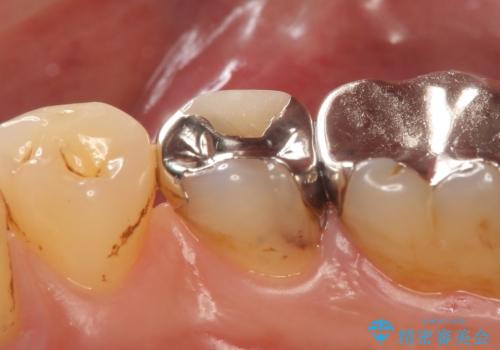

- 右下5番目の歯がしみるので診て欲しいといらっしゃった方の症例です。

古い銀歯及び虫歯を除去後、PGA(ゴールド)インレーによる修復を行いました。